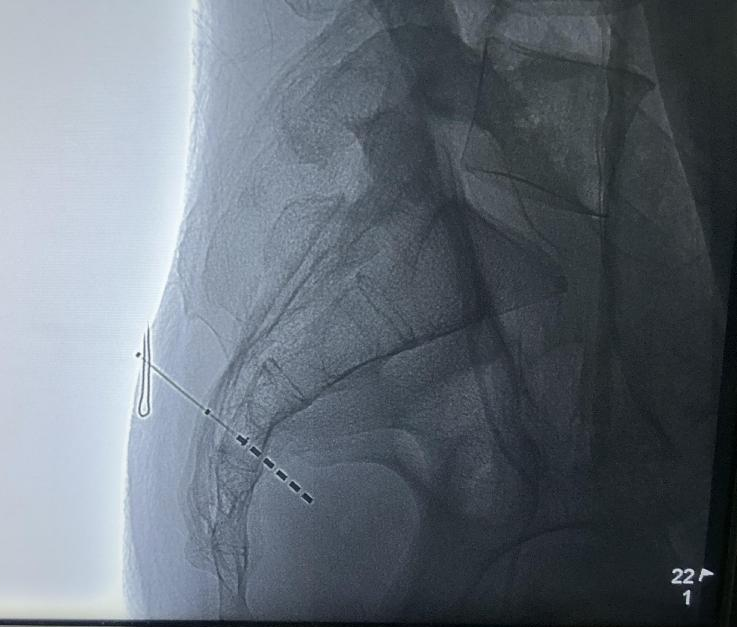

正在进行第三骶孔穿刺

2024年6月19日,方克伟教授、杨童欣博士、杨志忠医师等为患者实施了国产创新六触点骶神经调控一期电极植入术,手术过程顺利,一针穿刺即达目标,术中测试极低的电压即可出现良好的S3神经反应,电机位置佳。

术中点位图片